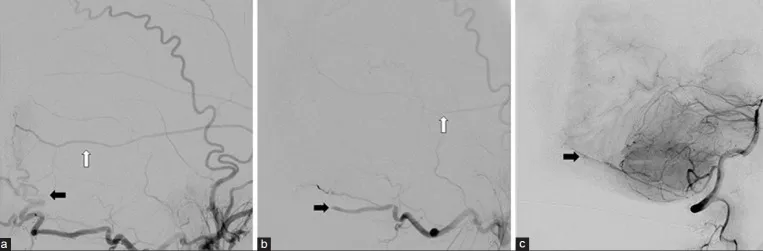

结扎正常的近端静脉窦,切开静脉窦及大脑镰至未受侵犯的直窦

切除受肿瘤侵犯的窦汇及左侧横窦结构,对右侧横窦及直窦的残留管壁进行一期修复

术前充分评估静脉引流途径,明确Labbe静脉的皮质静脉侧支引流和枕窦的深部结构静脉侧支引流